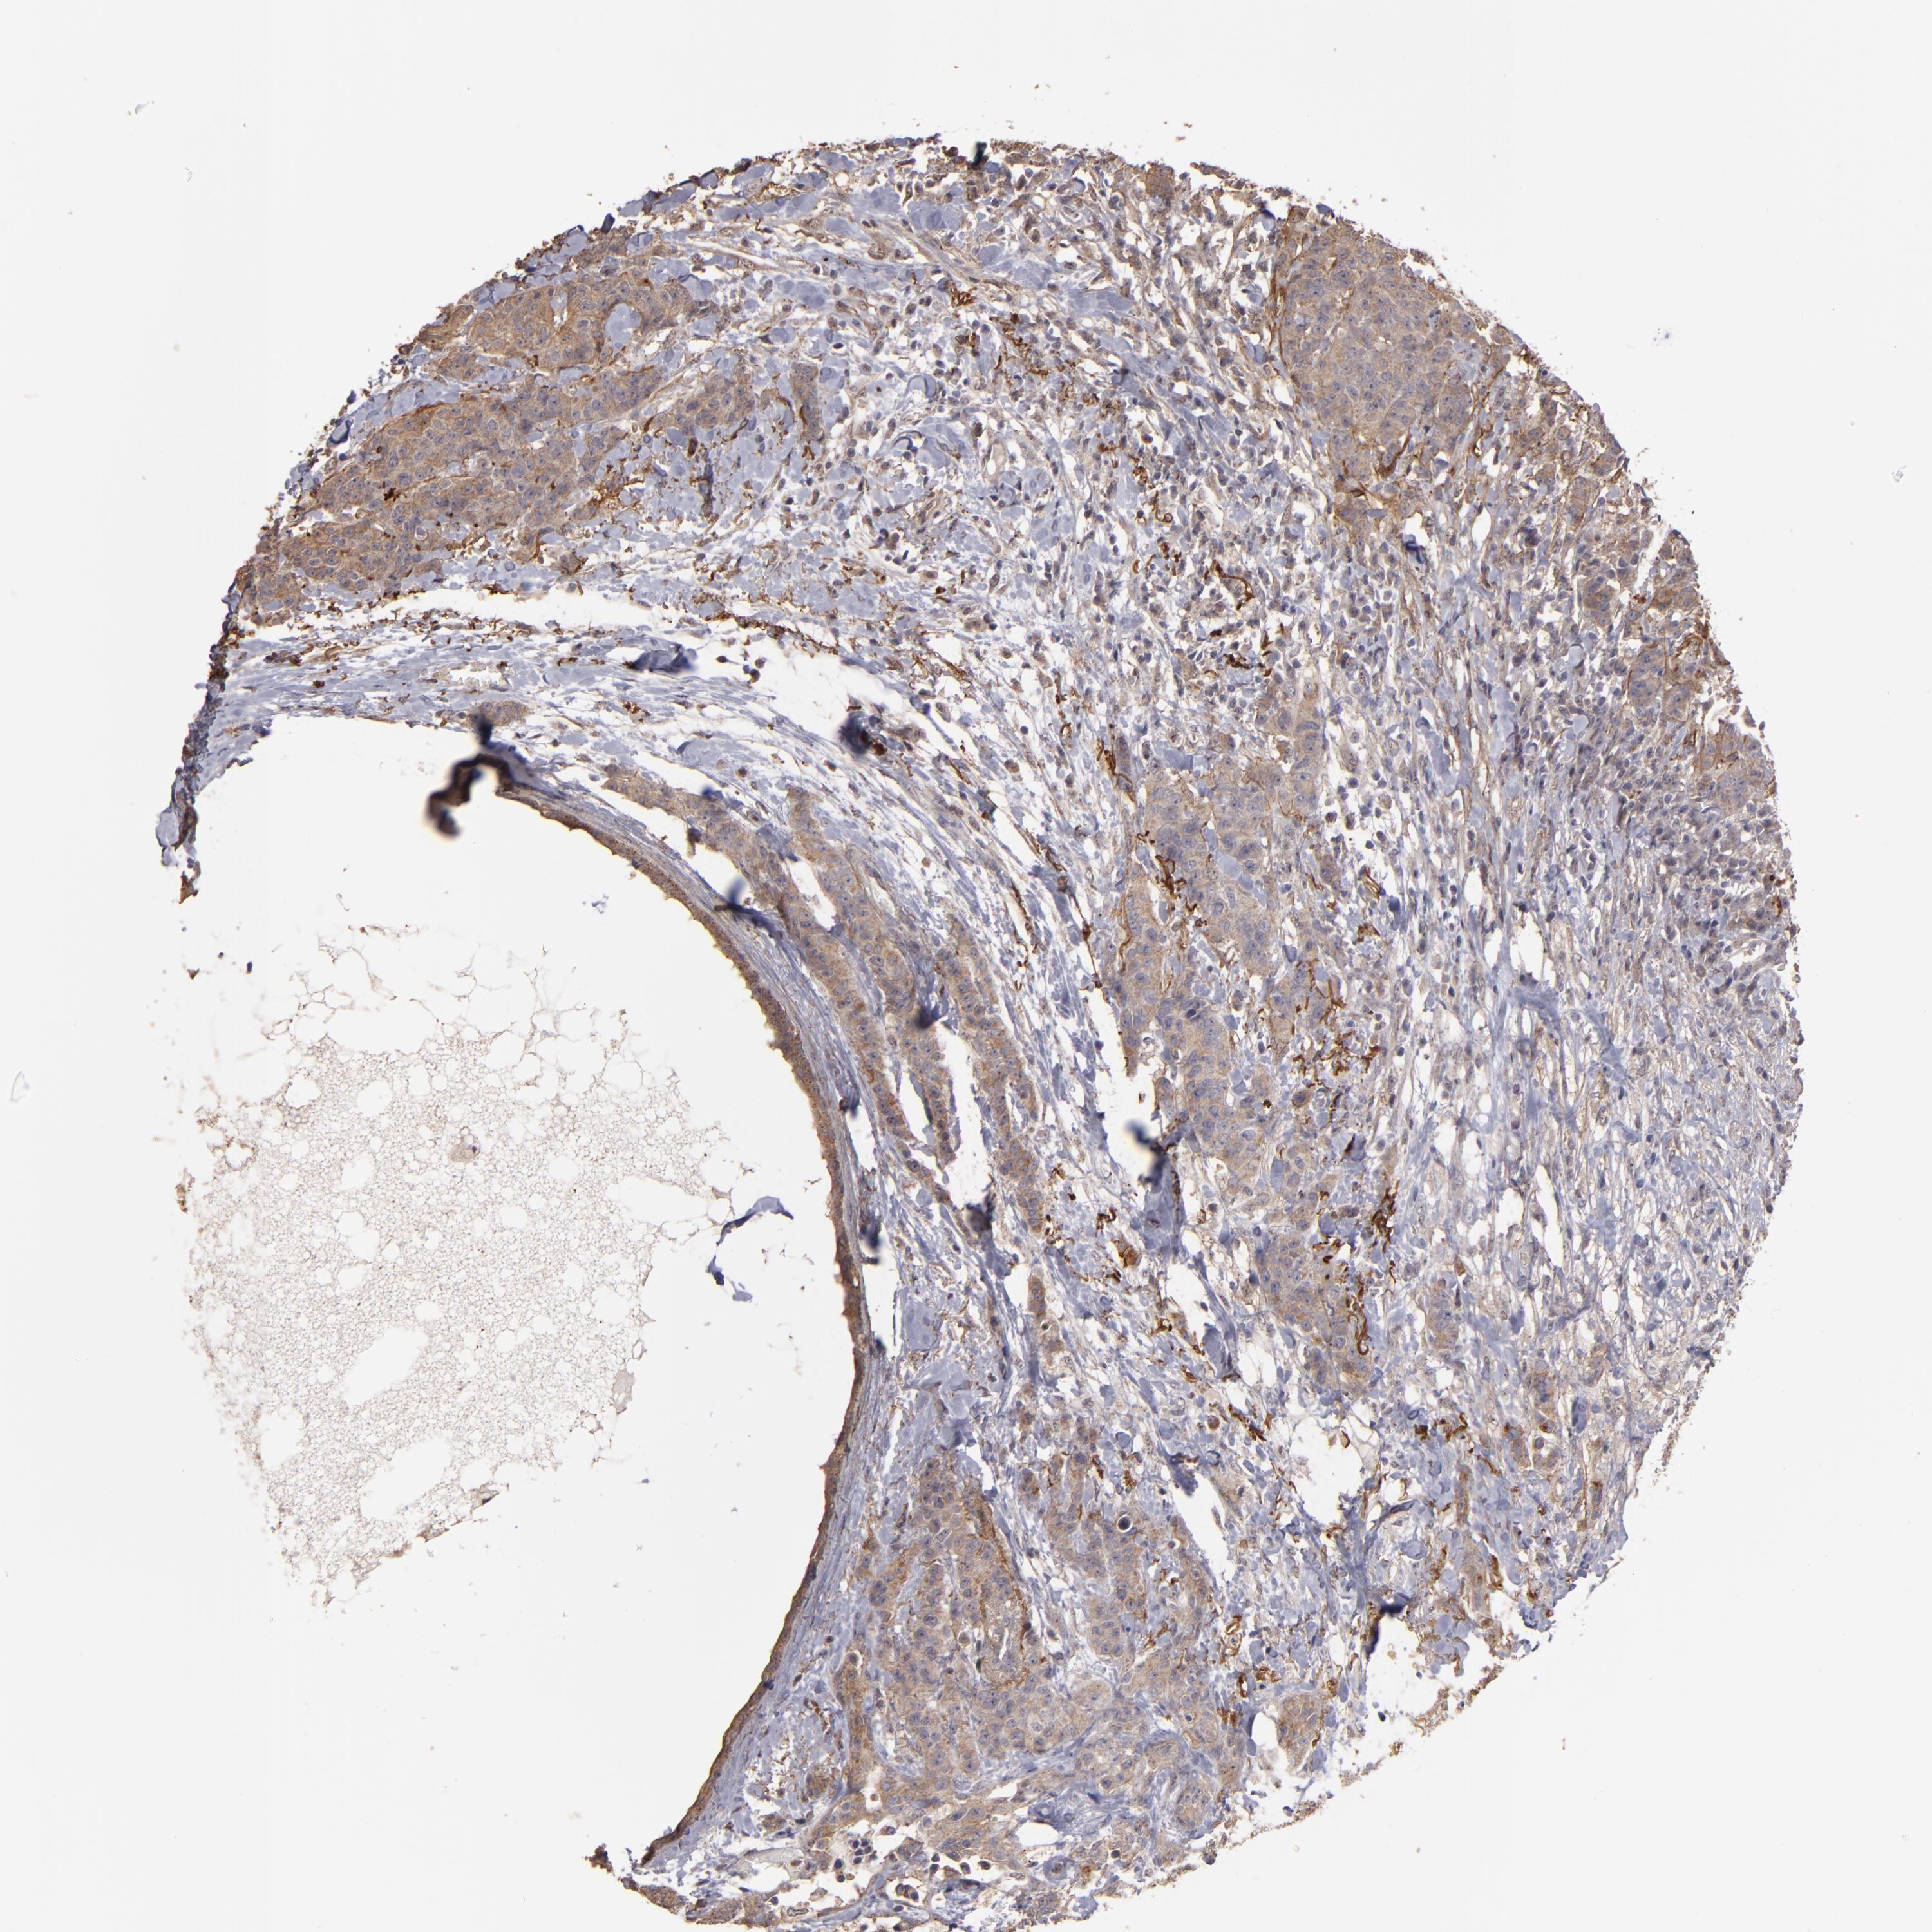

BRCA TCGA BRCA VALIDATION PROTEIN EXPRESSION

ANTIBODIES

AND

VALIDATION